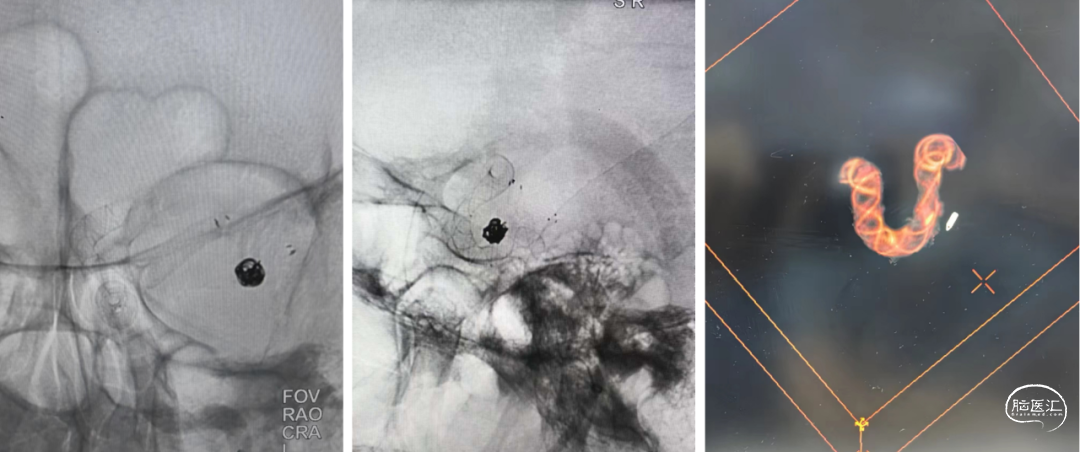

沿支架微导管输送Nuva®血流导向密网支架,待支架头端显影点与微导管齐平,支架输送到位,整体回撤微导管和支架至合适的锚定位置,在大脑中M1中段原位释放密网支架。

支架顺利打开,造形可见支架贴壁良好。

术后4个月复查造影示动脉瘤未愈合。

术后8个月复查CTA示夹层动脉瘤愈合。

1.该病例为多发脑动脉瘤、左侧颈内动脉末端夹层动脉瘤,动脉瘤近远端直径差较大血管迂曲,动脉瘤远端有脉络膜前动脉,传统支架金属填塞弹簧圈有闭塞脉络膜前动脉可能,且复发率较高。很难达到理想的栓塞效果。Nuva®血流导向密网支架操作简便,可以进行原位释放,30%-35%的金属覆盖率起到显著的血流导向作,有利于管腔重建,提高治愈率。

2.Nuva®血流导向密网支架创造性设计了输送系统释放段整体显影,清晰指示出血管真实走向,同时准确快速指示出可回收区域,为实现密网支架成功的释放提供了充分可靠的保障,有助于支架的成功释放。